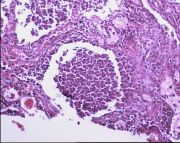

| 2021年12月10日 (五) 13:23 | 24号切片-小叶性肺炎-镜下观3.jpg (文件) |  |

154 KB | Cirno.9 | 基于MsUpload的文件上传 | 1 |